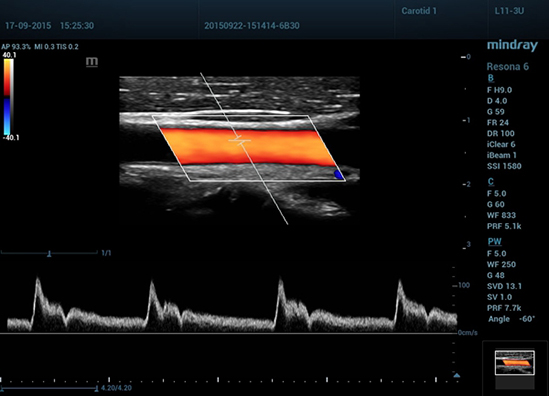

Клинические изображения Mindray Resona 6:

Mindray Resona 6 – экспертный УЗИ аппарат, позволяющий повысить качество диагностики за счет использования инновационных технологий, уникальной платформы ZST+, зонного сканирования и канальной обработке данных. Resona 6 повышает качество изображения, помогает в проведении диагностики, автоматически оптимизирует картинку при визуализации сложных областей — мелких сосудов или щитовидной железы.

Обеспечивая качество изображения уровня премиум, Resona 6 также повышает клинические возможности исследования при помощи революционной системы V Flow, предназначенной для оценки гемодинамических показателей сосудов; обеспечивает интеллектуальное получение из 3D данных наиболее важных проекций для диагностики ЦНС плода. Сочетая в себе интуитивно понятное сенсорное управление с распознаванием жестов и все важные клинические характеристики, передовая система Resona 6 настоящая новая волна в сфере ультразвуковых инноваций.